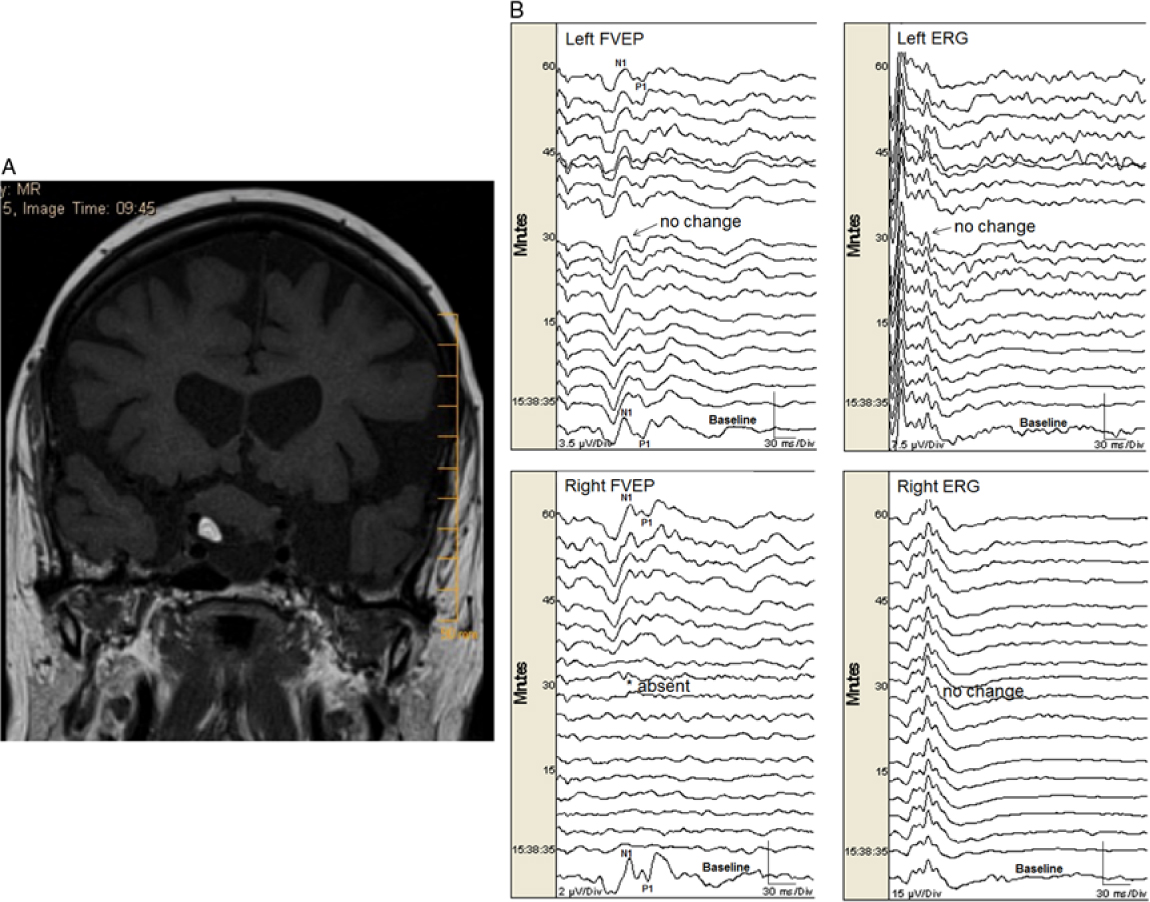

One eye (0.5%) with normal preoperative vision had a permanent FVEP loss (absent N1–P1 and subsequent FVEP waveforms, without change in ERG) during resection of a suprasellar tumor (Figure 1a and b). That eye had only light perception after surgery (a true positive). Seven eyes (4%) had transient FVEP N1–P1 amplitude decrease (without change in ERG) that was related to either manipulation of tumor, aneurysm, or nerve (see Table 2). All of those eyes did not have new postoperative visual deficits except one that had mild changes in visual acuity (and optic neuropathy) after clipping of a paraophthalmic aneurysm. In that case, the FVEP amplitude transiently decreased by 65% (to 35% of baseline) for a period of just under 10 minutes (while dissecting around the aneurysm) and returned fully to baseline amplitude following the event. There was no change in the ERG, indicating stable retinal stimulation (Figure 2). All of the other eyes had no significant change in FVEP N1–P1 amplitude and no new postoperative visual deficits (no false-negatives; Table 3). There were no false-positives. If we exclude the transient changers from our analysis, then the sensitivity is 1.0 (95% CI = 2.5, 100) and specificity is 1.0 (95% CI = 97.9, 100). If we include them, then the sensitivity is 0.5 (95% CI = 1.3, 98.8) and specificity is 1.0 (95% CI = 97.9, 100), respectively.

Figure 1: (A). A heterogeneous mass lesion in the suprasellar region (slightly more right of midline) measuring approximately 20 × 25 × 19 mm (AP × transverse × craniocaudal) likely splaying the optic nerves and chiasm. There was a focus of fat noted within the lesion. There was also an inferior cystic component. No significant enhancement noted in the post gadolinium images. (B). Permanent FVEP loss in this patient undergoing endonasal resection of a midline suprasellar teratoma. Preoperatively the patient had decreased visual acuity bilaterally with left worse than right eye. When working near the right optic nerve, the right FVEP was suddenly lost (bottom left panel). There was no change in the left FVEP (top left panel) and ERG bilaterally (top right and bottom right panels, respectively). At that time, the surgeon could not delineate a margin between the tumor and the nerve. Surgery ceased but the right FVEP remained absent. Postoperatively, the patient had worsened visual function in the right eye (only light perception) and improved visual function in her left eye.

Illustrative study showing permanent FVEP loss: A 77-year-old female with a history of multiple myeloma presented with bilateral visual loss over a period of 5 years but more recent progressive worsening of visual acuity in her left eye. Imaging revealed a suprasellar mass with heterogeneous content and significant chiasmal and optic nerve compression (more on the right side) (Figure 1a). She had an expanded endoscopic endonasal approach for tumor resection of the lesion, with dissection of the lesion from cranial nerves II and III as well as from the frontal lobes (pathology revealed a mature teratoma). Intraoperatively, there was a plane between the optic tract and the lesion bilaterally. Nevertheless, the most anterior part of the lesion was adherent to the right optic nerve, and traction on the lesion was associated with sudden FVEP loss (Figure 1b), so the procedure was aborted. The FVEP did not recover by the end of surgery. Postoperatively, she had only light perception in the right eye, while visual acuity improved in her left eye.

Our FVEP findings relate strongly to visual outcome. We had one eye with permanent FVEP loss associated with severe deterioration of visual function (0.5% of all eyes monitored) and one eye with transient FVEP change associated with mild postoperative deterioration of visual acuity (0.5% of all eyes monitored). In the former case, the right FVEP N1–P1 (and all subsequent FVEP waveforms) permanently disappeared (Figure 1b). At that time, the margin between optic nerve and tumor was ill-defined. The surgeon was promptly informed of the FVEP loss and he stopped resecting and retracting, but the FVEP did not return. In contrast, we had seven eyes (4%) with significant transient FVEP amplitude deterioration related to surgical manipulation. In all of those cases the surgeon was promptly informed of the FVEP deterioration and stopped resecting and/or retracting near the offended optic nerve or chiasm. The FVEP amplitude recovered within 10–15 minutes in all cases (Table 2). All but one of those eyes had unchanged postoperative visual function (one had a mild deterioration in visual acuity postoperatively despite full recovery of the FVEP). Accordingly, we believe prompt reporting of FVEP deterioration resulted in prompt surgical action that was important for FVEP amplitude recovery, which, in turn, may have accounted for the low postoperative visual deficit rate (1%) in this series. We believe that transient change should be excluded from the analysis of sensitivity and specificity because it reflects functional compromise of the visual pathway that is undergoing some degree of recovery and, as such, is not categorically a positive or negative finding. Consequently, our sensitivity and specificity were 1.0 (excluding the transient changers).